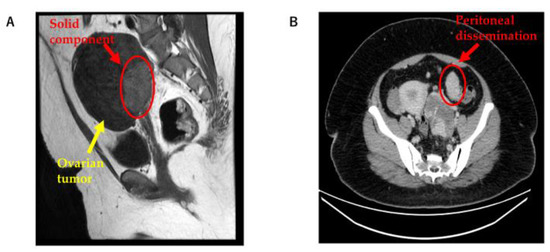

A multiple cystic mass was detected in the left ovary by transvaginal ultrasonography. To further investigate the left ovarian tumor, magnetic resonance imaging (MRI) and computed tomography (CT) were performed. MRI showed a solid component in the left ovarian tumor, and CT showed peritoneal dissemination (Figure 1A,B). Ovarian cancer was suspected based on the medical examination and imaging findings. Therefore, open surgery was selected as the treatment.

Figure 1.

(A) MRI showing a solid component in the left ovarian tumor; and (B) CT showing peritoneal dissemination. MRI: magnetic resonance imaging; CT: computed tomography.